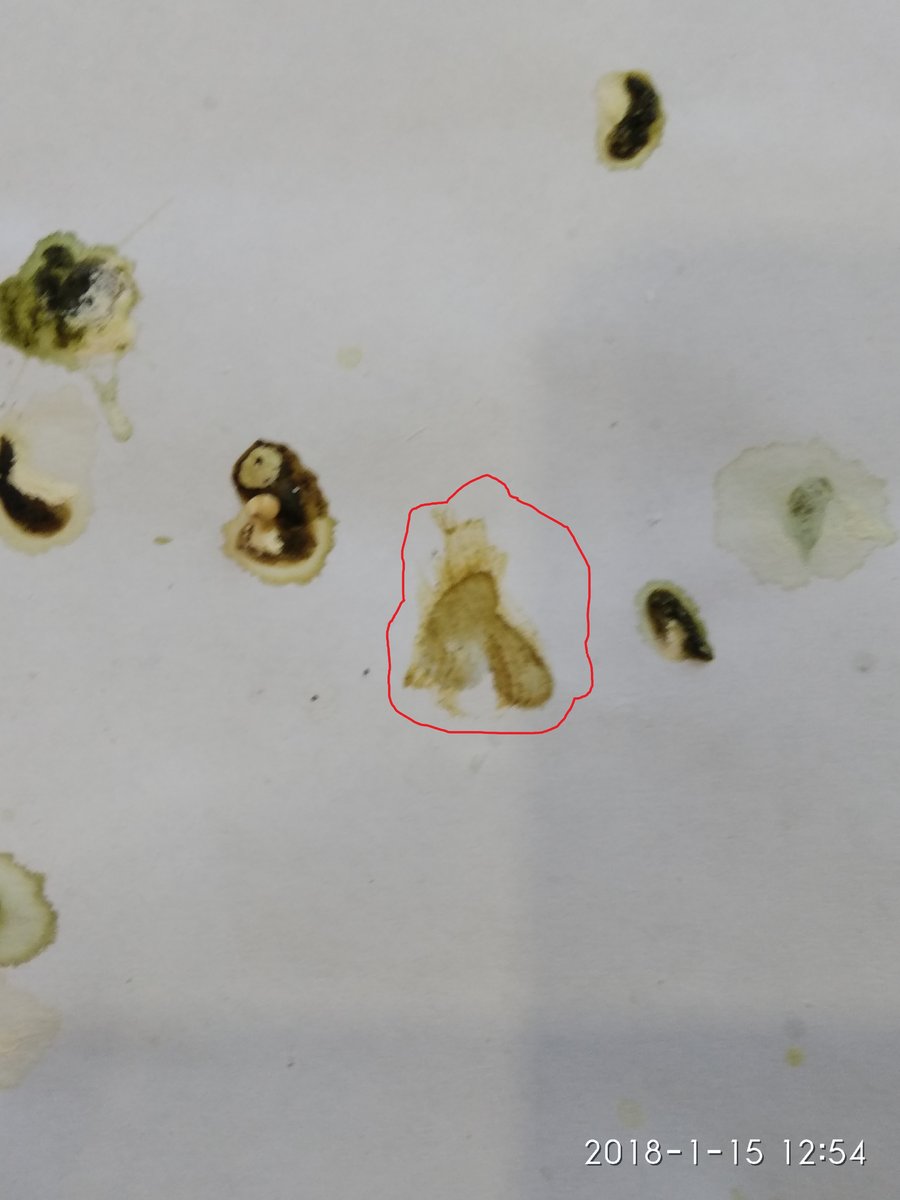

Помёт птички последний.

1-ое фото- под подозрением на проблемы с печенью.

2-ое - фото когда какаху убрала. КОРИЧНЕВЫЙ!!!!

Последняя какаха - ( фотки нет) - Цвет совершенно другой. Зеленый.

Если ориентироваться на 1- ое и 2-ое фото,

Думаю можно Гепатовет давать? Или ещё подождать?